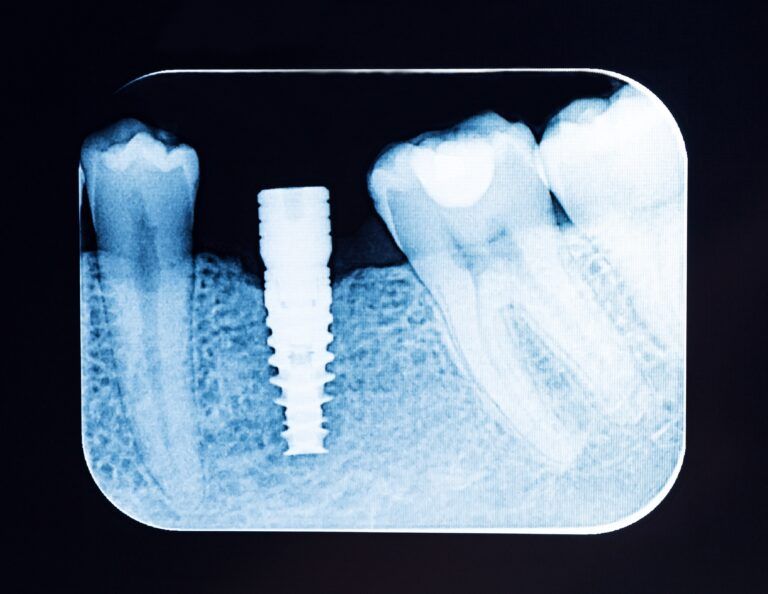

Periapical X-Rays: Essential Imaging for Dental Implant Planning

Periapical X-rays play a pivotal role in the realm of dentistry, serving as an essential imaging tool that goes beyond mere diagnosis to assist in meticulous planning for dental implants. These radiographs offer a close-up view of the entire tooth—from

The Importance of Diagnostic Imaging for Dental Implant Success

In the world of modern dentistry, dental implants have emerged as a game-changer, offering durable and natural-looking solutions to tooth loss. However, the key to their success lies in meticulous planning and precision, primarily driven by diagnostic imaging. These images